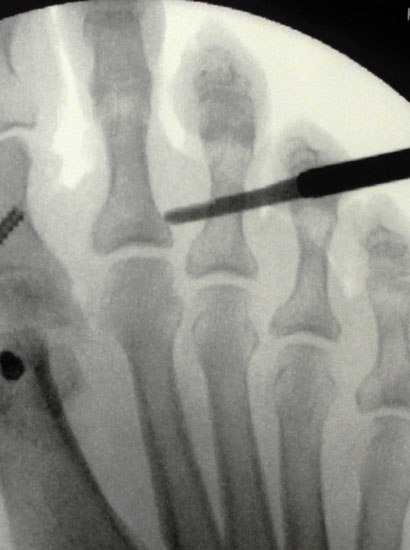

Mit dem MIS-Messer und dem Bildwandler erfolgt nun eine Positionskontrolle zur korrekten Lokalisation auf Höhe des proximalen metadiaphysären Überganges des Grundgliedes (Abb 4).

Im Anschluss erfolgt das Einbringen der Fräse nach plantar unter das Grundglied, auf steten Knochenkontakt sollte geachtet werden. Unter Bildwandler sollte zusätzlich zur korrekten metadiaphysären Lokalisation der Osteotomie  auch auf eine Positionierung der Fräse im rechten Winkel zum Schaft geachtet werden, zusätzlich darauf, dass zum Schutz des Gefäßnervenbündels der Gegenseite die Fräse nicht zu weit über die geplante Osteotomie  auf der  Gegenseite über das Grundglied herausragt.

Für reproduzierbare Ergebnisse scheinen uns folgende Punkte im intra- und postoperativen Verlauf wichtig: Unser operatives setup berücksichtigt die Tatsache, dass während der Operation mehrfach durchleuchtet werden muss. Durch die schräge Positionierung des Bildverstärkers unter dem frei zugänglichen Fuss während der gesamten OP entfallen zeitaufwändige Repositionierungen des Bildverstärkers und die einmal eingestellte Ebene bleibt erhalten. Auch bei guten Anatomiekenntnissen und palpablen Strukturen empfiehlt sich eine mehrfache Durchleuchtung zur Überprüfung der korrekten Positionierung von Inzision,  Raspel und anschließend der Fräse. Bei der Positionierung der Fräse sollte bei der Hammerzehenkorrektur ohne Abweichung in der Transversalebene streng auf eine Lage im rechten Winkel zur Knochenachse geachtet werden. So können unbeabsichtigte Abweichungen in dieser Ebene nach schräg durchgeführten Osteotomien vermieden werden.